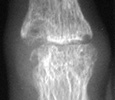

The earliest signs of the disease process are periarticular soft tissue swelling

due to effusion, tenosynovitis and edema. Joint spaces may actually widen

in the early stages of RA. Periarticular osteopenia can also be seen. Early

articular changes occur at the "bare area" of small joints, which

are not covered by cartilage. These marginal erosions are often first seen

at the 2nd and 3rd MCP and the 3rd PIP articulations.

Advanced signs of RA include diffuse loss of joint space due to loss of cartilage. There can also be marginal or central erosions and severe joint deformities. Subluxations and dislocations may lead to ulnar deviation at the MCP joints and radial deviation at the radiocarpal articulations of the wrists. Erosive changes are also noted at the distal ulna and radial styloid. Joint deformities seen in RA include a Boutonniere deformity (flexion at the PIP joint and hyperextension at DIP joint) and a Swan-neck deformity (hyperextension at the PIP joint and flexion at the DIP joint). In severe cases, there may be radiographic findings of ankylosis at the proximal interphalangeal and metacarpophalangeal joints.